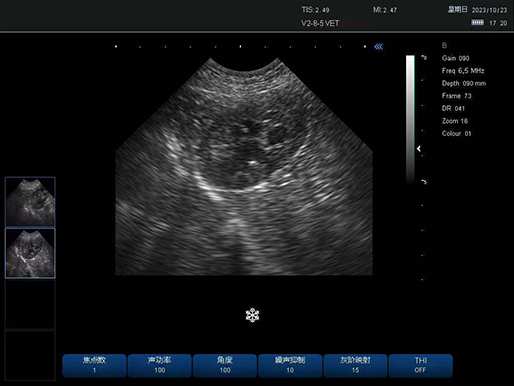

犬 肾脏

犬 肾脏

有关病变的更多见解

凸阵探头-犬 肾脏

凸阵探头-犬 肾脏